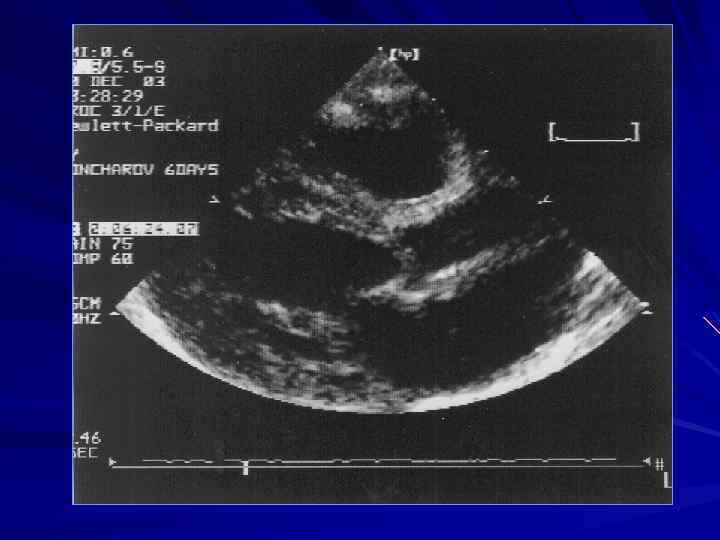

Гемодинамика аортального стеноза У новорожденных с тяжелой обструкцией выводного тракта и недостаточно гипертрофированным ЛЖ (критический аортальный стеноз) синдром низкого сердечного выброса реализуется в первые дни после рождения. При этом градиент давления на клапане может быть небольшим, что создает иллюзию небольшого стеноза. При резком снижении АД в подобных ситуациях кровь в системный кровоток может попадать из ЛА через ОАП. Поступление венозной крови в аорту приводит к центральному цианозу, симулирующему «синий» порок сердца.

Врожденный клапанный аортальный стеноз При сканировании сердца обращают внимание на диаметр клапанного кольца аорты, количестворок клапана, их раскрытие, деформацию, сращение по комиссурам, диаметр и площадь эффективного отверстия.

Врожденный клапанный аортальный стеноз Специфическим симптомом является дугообразное выбухание створок в просвет аорты с турбулентным потоком крови через аортальный клапан

Врожденный клапанный аортальный стеноз Допплерография дает представление об уровне максимальной обструкции и приблизительную оценку тяжести стеноза Однако, градиент давления в значительной мере зависит от величины сердечного выброса и может значительно изменяться при СН, ФН, беспокойстве ребенка.

Врожденный клапанный аортальный стеноз Дополнительно проводят оценку гипертрофии миокарда левого желудочка, его систолических и диастолических параметров

Врожденный клапанный аортальный стеноз Анализируются вторичные изменения: аортальная регургитация, постстенотическая дилатация аорты, митральная недостаточность

ЭХО - КГ ДИАМЕТР КЛАПАННОГО КОЛЬЦА КОЛИЧЕСТВО И МОРФОЛОГИЯ СТВОРОК КЛАПАНА ГРАДИЕНТ СИСТОЛИЧЕСКОГО ДАВЛЕНИЯ НЕДОСТАТОЧНОСТЬ АОРТАЛЬНОГО КЛАПАНА ОБЪЁМ, СОКРАТИМОСТЬ И ТОЛЩИНА СТЕНКИ ЛЕВОГО ЖЕЛУДОЧКА ФИБРОЭЛАСТОЗ ЭНДОКАРДА МОРФОЛОГИЯ И ФУНКЦИЯ МИТРАЛЬНОГО КЛАПАНА